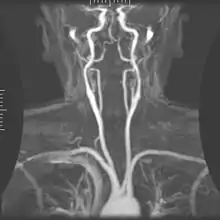

Angiography

Magnetic resonance angiography

Magnetic resonance angiography (MRA) generates pictures of the arteries to evaluate them for stenosis (abnormal narrowing) or aneurysms (vessel wall dilatations, at risk of rupture). MRA is often used to evaluate the arteries of the neck and brain, the thoracic and abdominal aorta, the renal arteries, and the legs (called a "run-off"). A variety of techniques can be used to generate the pictures, such as administration of a paramagnetic contrast agent (gadolinium) or using a technique known as "flow-related enhancement" (e.g., 2D and 3D time-of-flight sequences), where most of the signal on an image is due to blood that recently moved into that plane (see also FLASH MRI).[51]

Techniques involving phase accumulation (known as phase contrast angiography) can also be used to generate flow velocity maps easily and accurately. Magnetic resonance venography (MRV) is a similar procedure that is used to image veins. In this method, the tissue is now excited inferiorly, while the signal is gathered in the plane immediately superior to the excitation plane—thus imaging the venous blood that recently moved from the excited plane.[52]